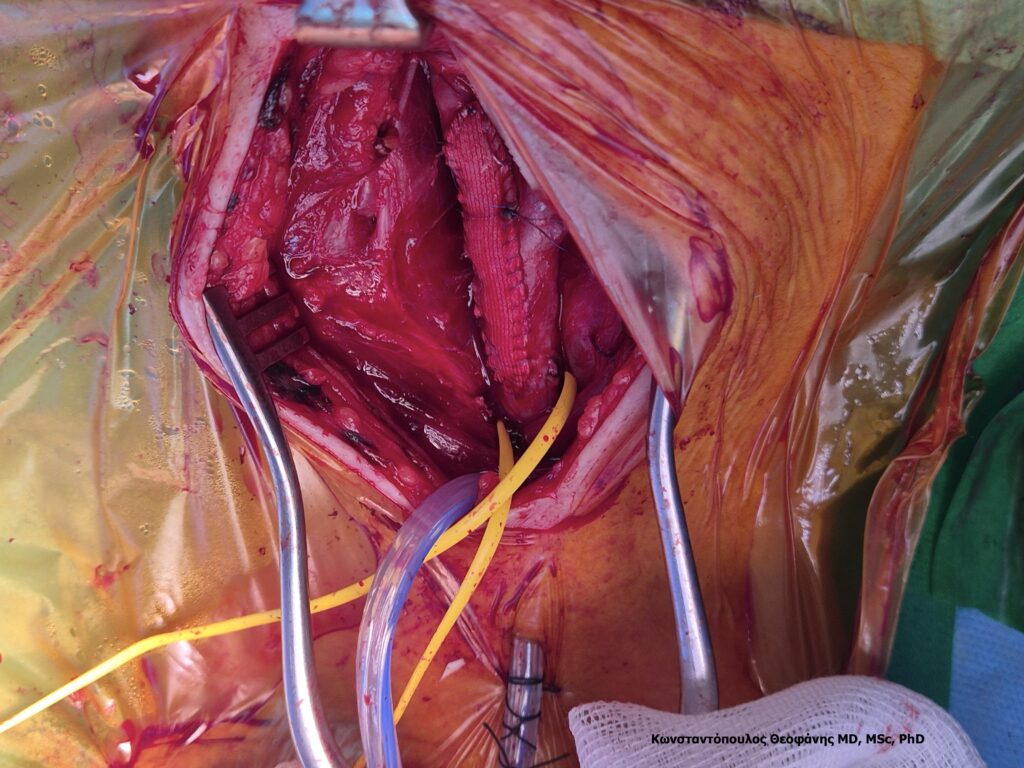

Η χειρουργική επέμβαση βήμα προς βήμα

Η ενδαρτηρεκτομή πραγματοποιείται με γενική ή τοπική αναισθησία. Ο αγγειοχειρουργός κάνει τομή στο πλάγιο του τραχήλου μήκους περίπου δέκα εκατοστών. Αφού απομονωθεί η καρωτίδα, διακόπτεται προσωρινά η ροή και αφαιρείται η αθηρωματική πλάκα. Η αρτηρία ράβεται είτε άμεσα είτε με τη χρήση ειδικού εμβαλώματος, ώστε να εξασφαλιστεί επαρκής διάμετρος. Σε ορισμένες περιπτώσεις εφαρμόζεται τεχνική αναστροφής (eversion). Η διάρκεια της επέμβασης κυμαίνεται συνήθως από μία έως δύο ώρες.